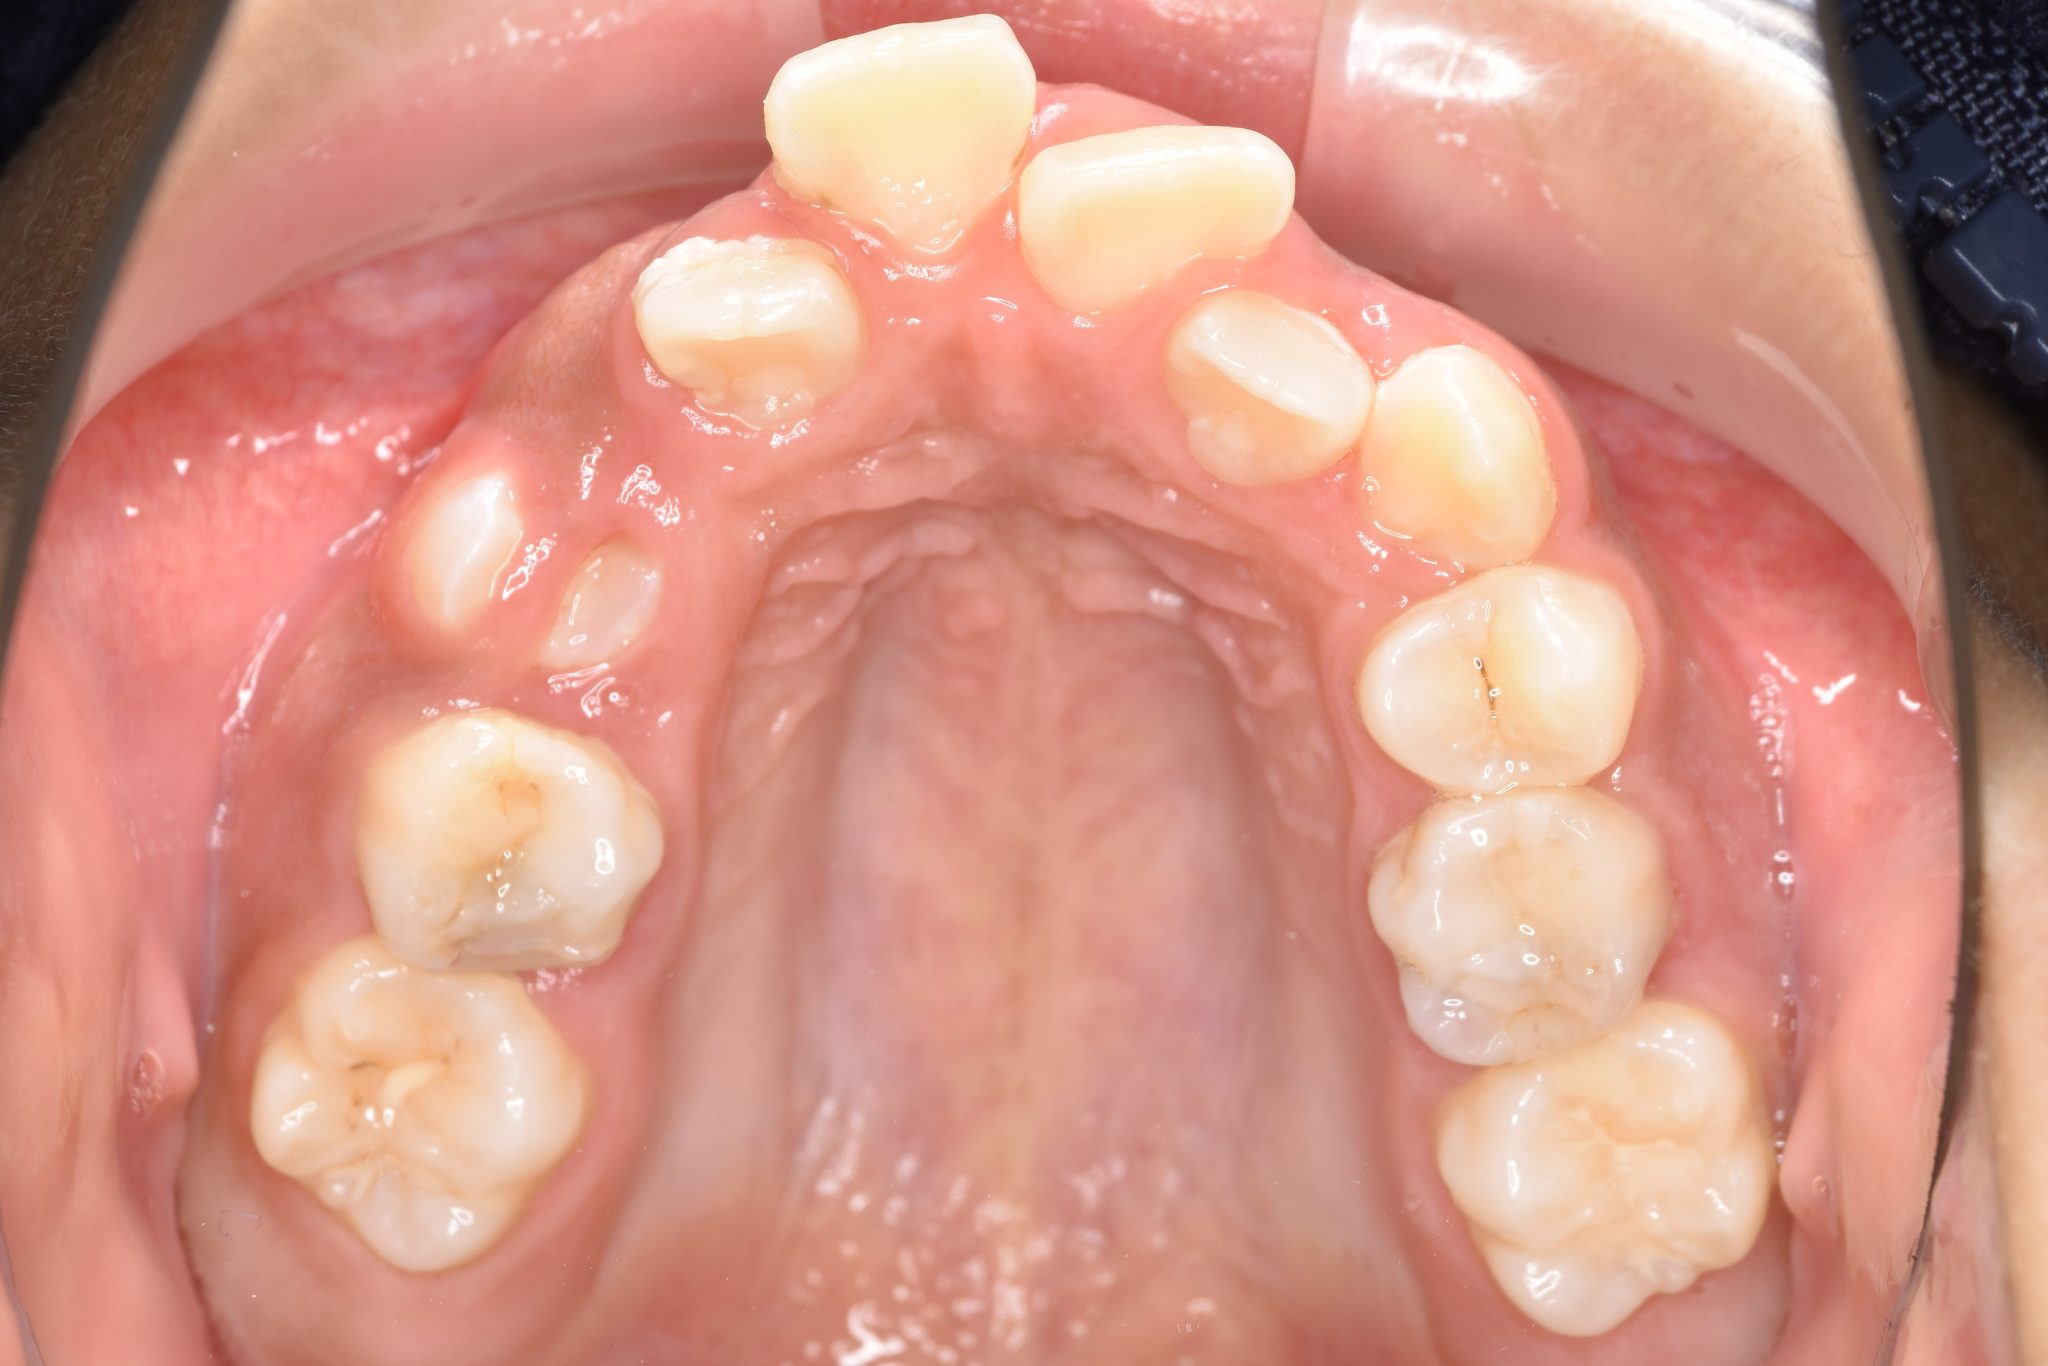

ビフォー

全顎ワイヤー矯正 症例_474

主訴 歯並びがガタガタで前歯が出ている

施術内容 小児矯正1期治療

治癒期間 1年5か月間

費用 1,020,800円(税込)